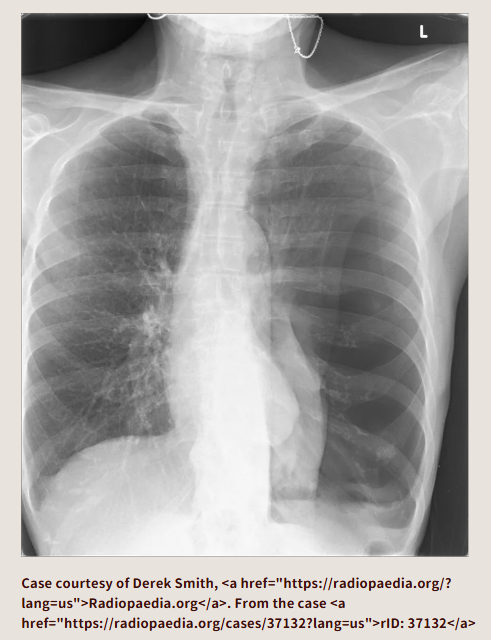

この胸部レントゲン画像はどうでしょうか? ぱっと見て思うのは、おそらくモニター心電図の電極が付いていて、左の肺が白ぽいので肺炎かな、状態悪そうだなということです。気胸はどこにあるでしょうか?

右肺が気胸になっています。